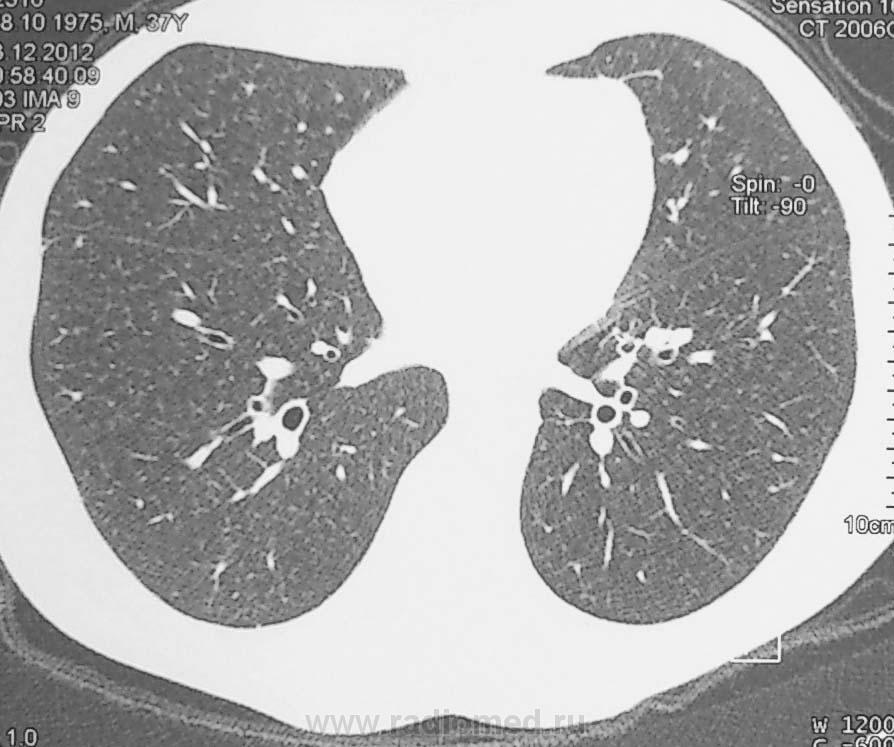

В  терапевтическое отделени поступил мужчина 1975 г.р. с жалобами на кашель и повышение температуры тела, на рентгенограмме от 26.12.12г.

После курса антибактериальной терапии изменения сохраняются:

Добавлены изображения КТ.

Сразу предположил ретенционную кисту. Посмотрев КТ и увидел связь с бронхососудистым пучком, думаю, что мальформация. Контраст вводили?

А вот тут контрастное КТ-исследование необходимо, чтоб отличить сосудистую мальформацию. И послушать под лопаткой, соотнести клинику и картинку. Возможно, что лёгочные жалобы - банальное ОРВИ, не имеющее отношение к патологии нижней доли. Мне понятнее не стало, хочется dicom КТ-исследования  с контрастом.

Из заключения по КТ: Характер выявленных изменений в нижней доле правого легкого неясен, наиболее вероятно объемное образование перефирического характера. Рекомендуется проведение бронхоскопии и морфологическая верификация.

Нагноившиеся (?) ретенционные кисты S 10 справа. Д/диагностика с мальформацией, гипоплазией сегмента, локальными буллами. Туб никто не отменял.